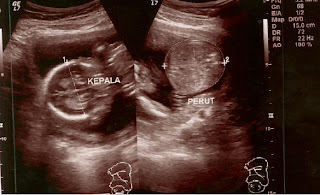

usg 2 dimensi dedek 18 minggu

Akhirnya baru kesampaian posting foto usg 2 D nya dedek, foto ini diambil waktu pulang ke surabaya, di usg sendiri ma mbak yang kebetulan dines di gleneagles surabaya.